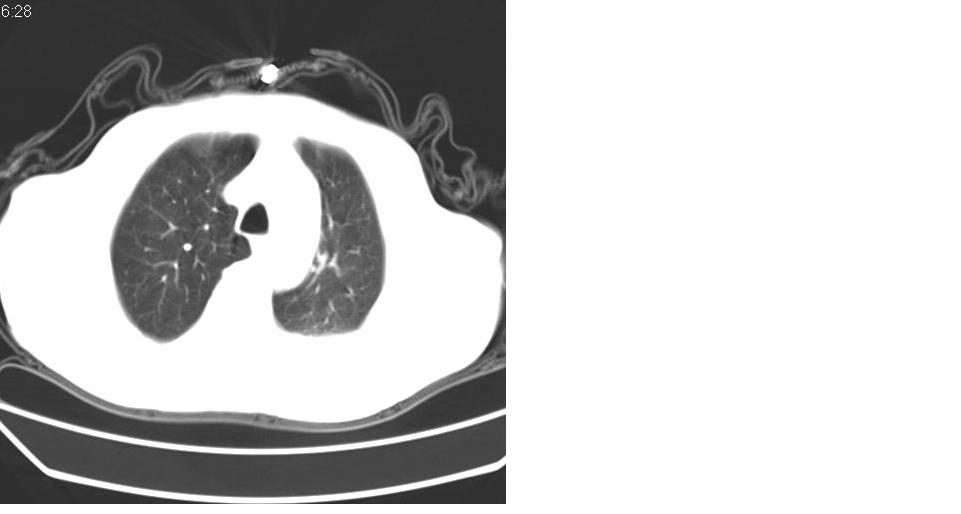

左肺下叶略萎陷、实变,内可见含气支气管征。左舌叶、中叶亦见少许斑片状高密度区,边界不清。纵隔未见肿大淋巴结影。

左下肺体积缩小,密度增高,见片增密影。边界模糊,见支气管充气像,肺门纵隔无异示,心脏气管左移,左侧胸腔少量积液。考虑肺部感染伴部分肺不张[有脑梗塞病史坠积性肺炎可能]

左下肺体积缩小,密度增高,并见大片状致密影,边界模糊,其内见支气管充气像,肺门纵隔无异常,心脏气管左移,左侧胸腔少量积液。考虑:左肺炎性病变伴不张。

左肺下叶感染,肺膨胀不全,左胸腔积液,不能排除结核性病变